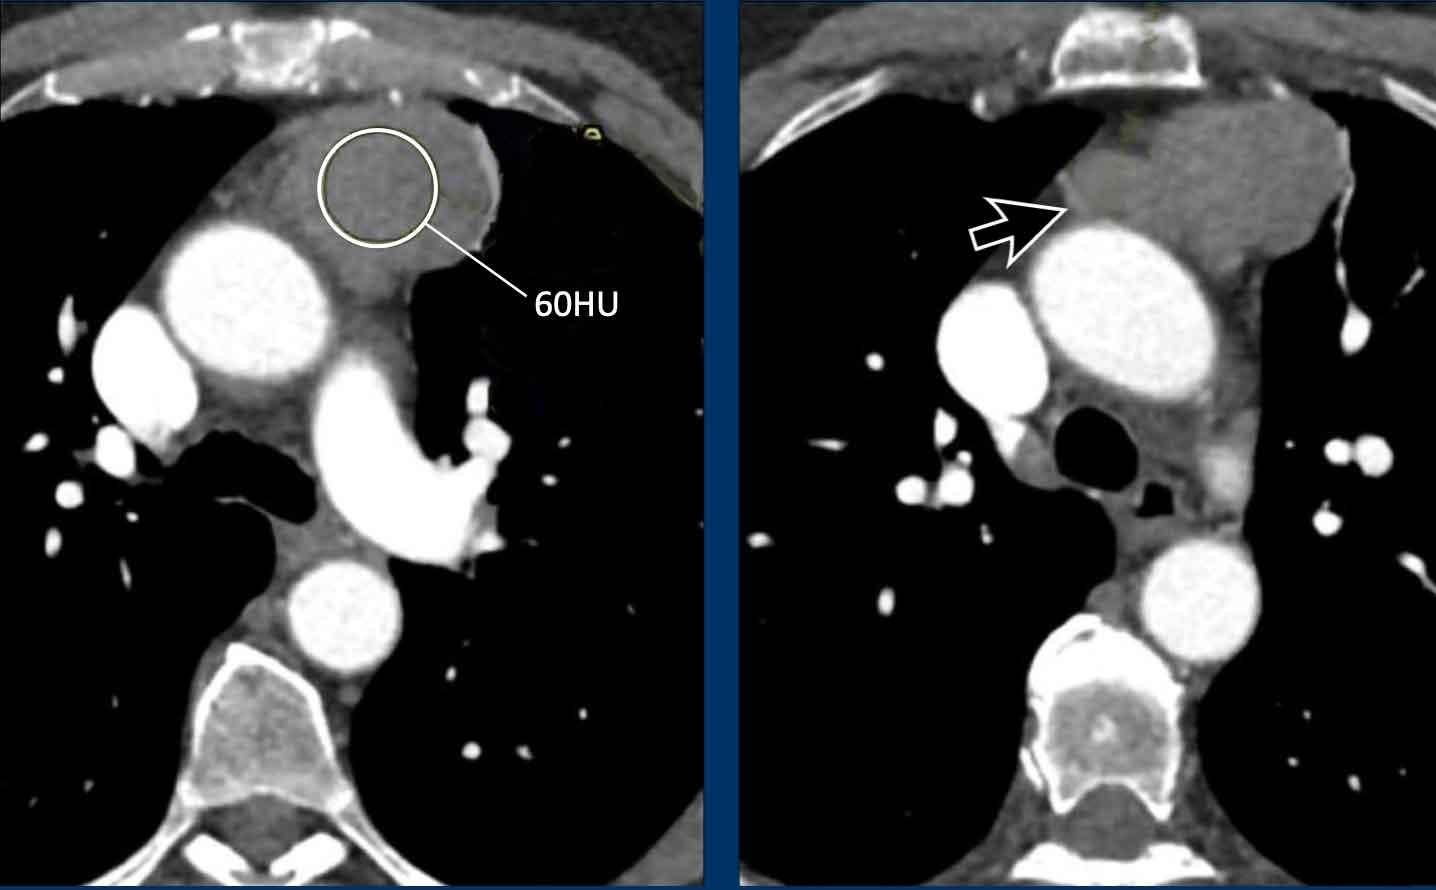

Các hình ảnh này của một nam giới 71 tuổi.

Trên CT ngực, tình cờ phát hiện một khối ở tuyến ức.

Hãy phân tích các hình ảnh. Nhận định của bạn là gì?

Hình ảnh

Một phần tổn thương có ngấm thuốc cản quang và có một số vôi hóa, có thể nằm ở thành nang.

Khi một tổn thương tuyến ức có thành phần đặc, nguyên tắc là… “khi còn nghi ngờ, hãy phẫu thuật cắt bỏ”.

Tổn thương đã được phẫu thuật cắt bỏ dựa trên kết quả CT và kết quả giải phẫu bệnh cho thấy đây là u tuyến ức dạng nang.

Nang so với u tuyến ức dạng nang

Nang có thể có ngấm thuốc nhưng chỉ giới hạn ở thành nang mỏng.

Không được có các nốt hoặc thành phần đặc.

Đôi khi việc phân biệt này rất khó khăn và trong những trường hợp như vậy, nên theo dõi định kỳ, đầu tiên sau 6 tháng và sau đó hàng năm cho đến 5 năm.

Việc theo dõi có thể thực hiện bằng MRI hoặc trong một số trường hợp bằng CT.